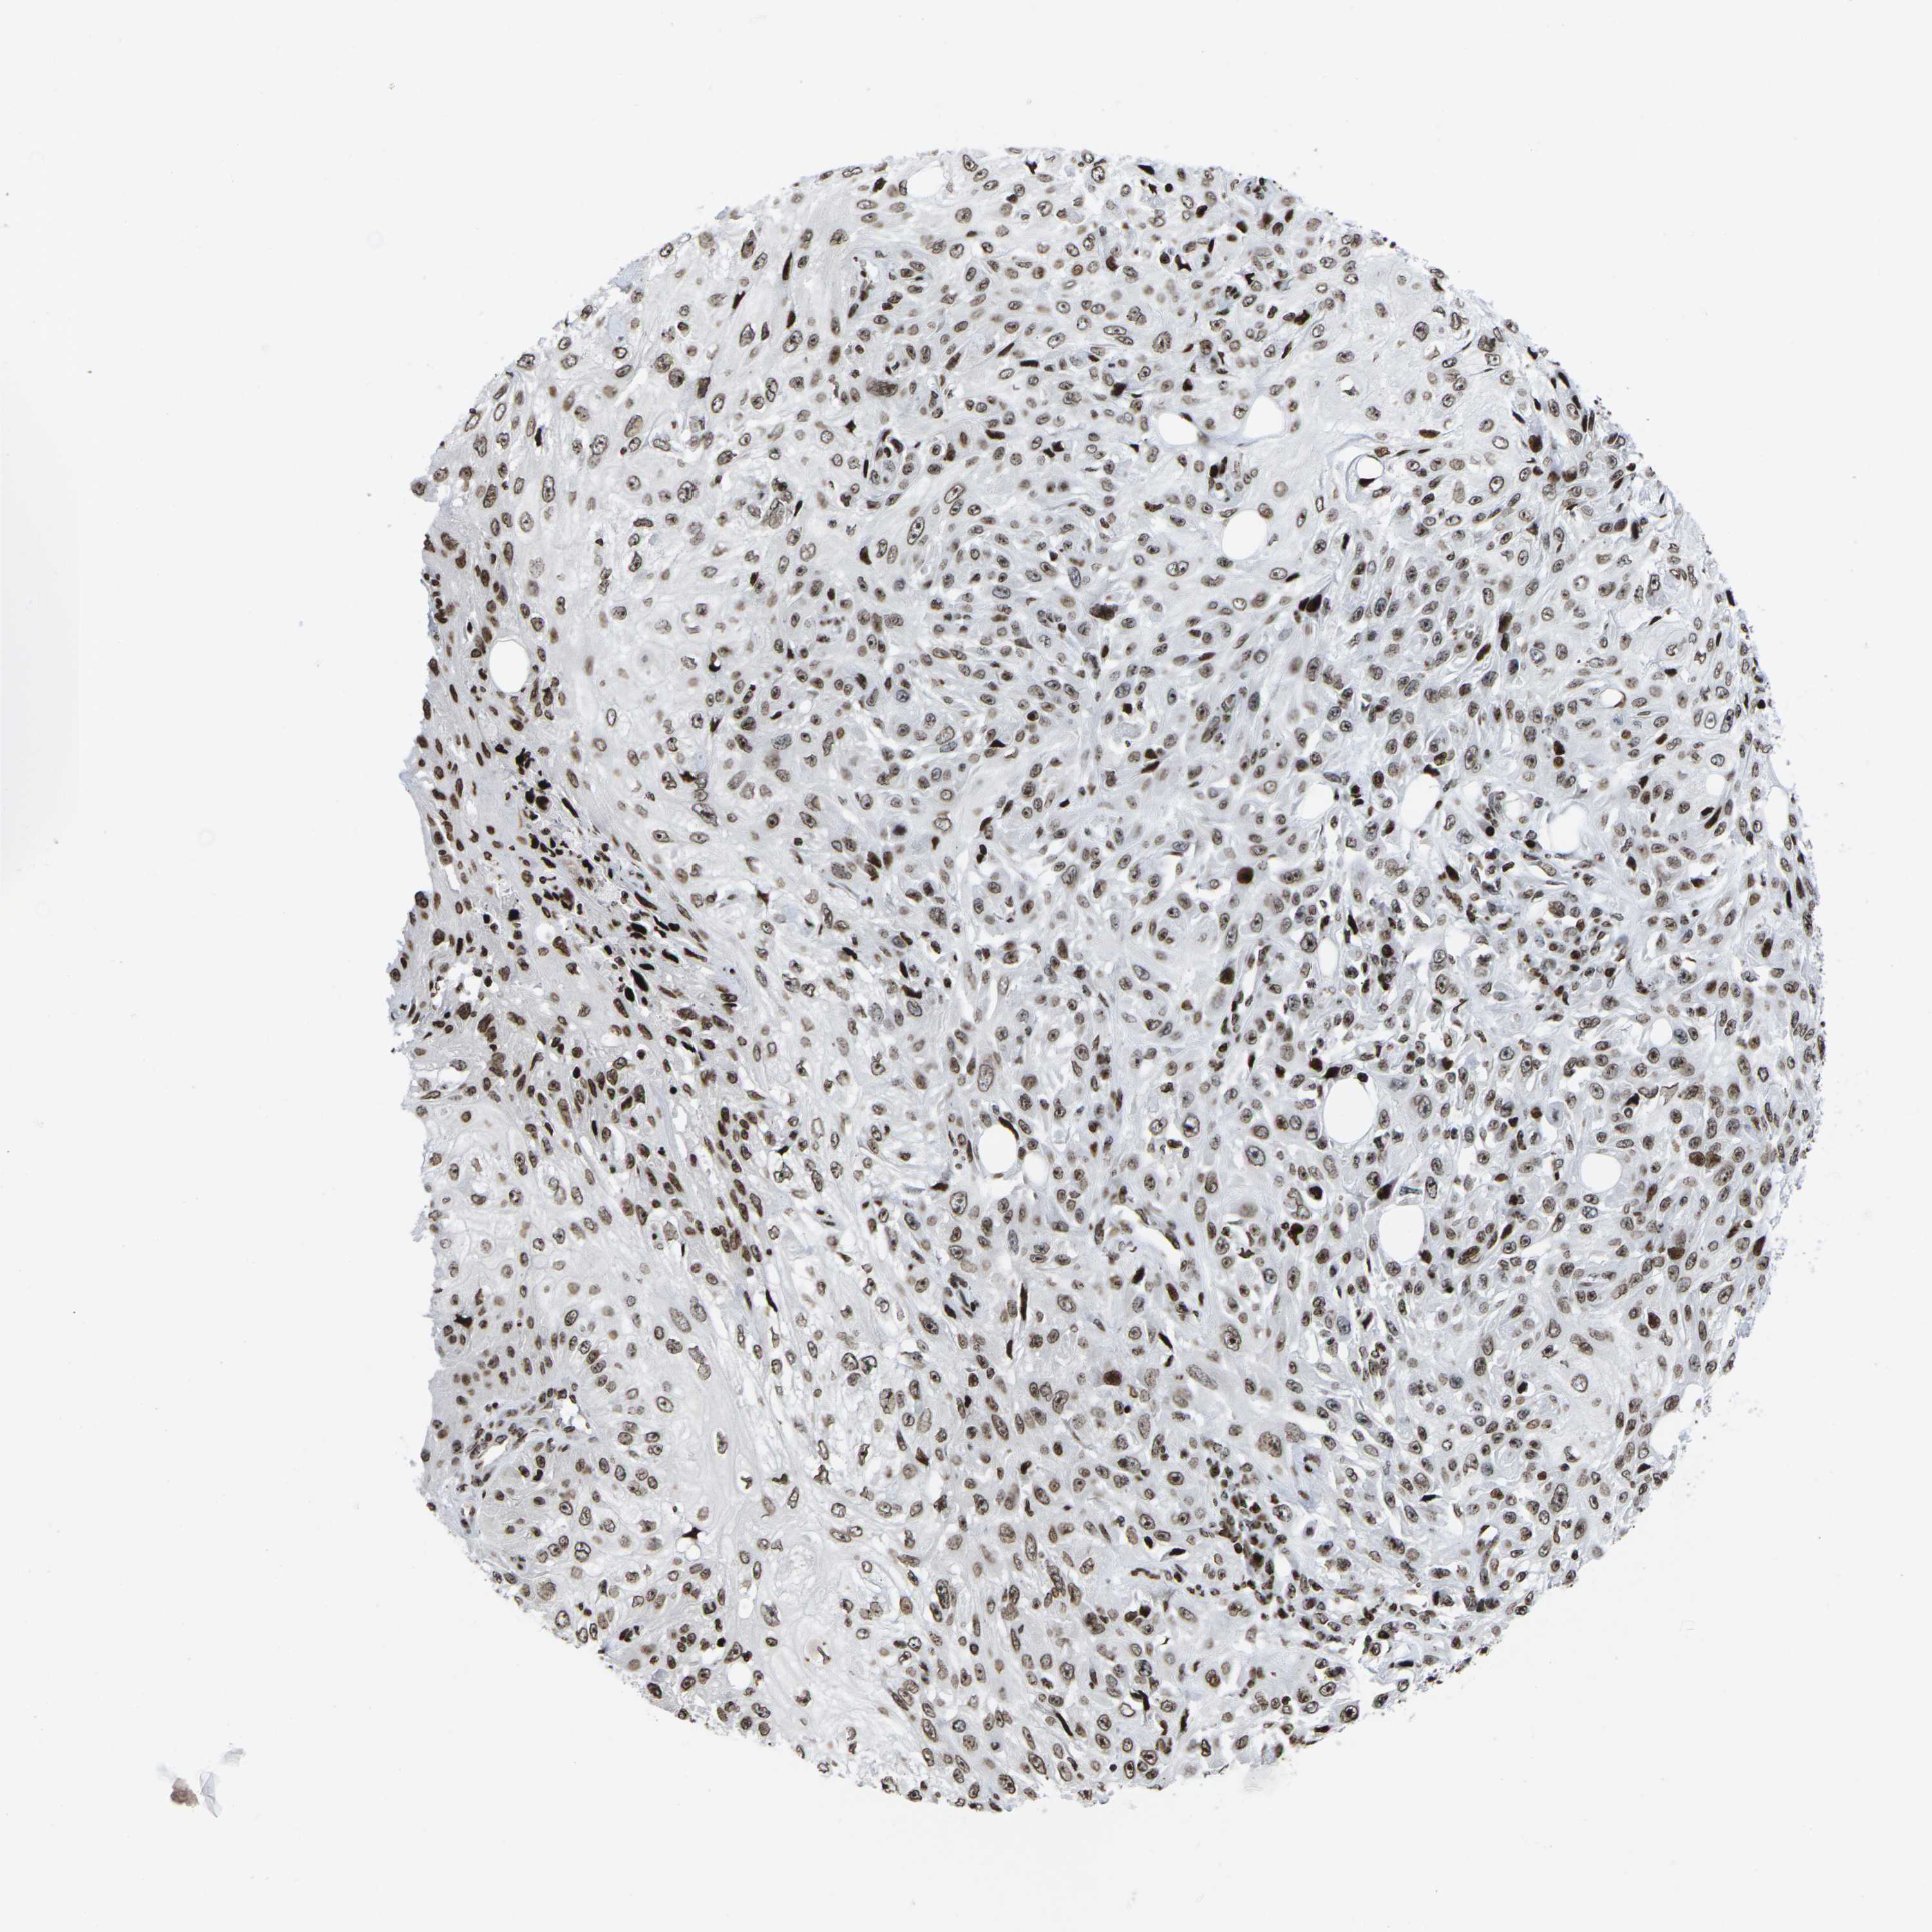

SKIN CANCER - Protein expressioni

A mouse-over function shows sample information and annotation data. Click on an image to view it in a full screen mode. Samples can be filtered based on level of antibody staining by selecting one or several of the following categories: high, medium, low and not detected. The assay and annotation is described here.

Each image is clickable and will lead to virtual microscopy that enables deeper exploration of all samples and also displays staining intensity scores, fraction scores and subcellular localization as well as patient and tissue information for each sample.

Antibody HPA055907

Squamous cell carcinoma, metastatic, NOS